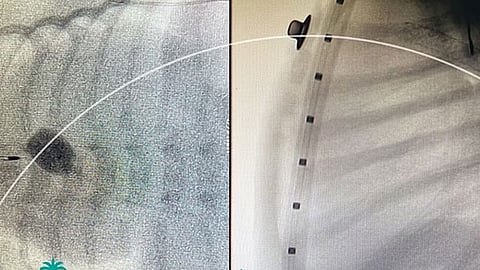

أنقذت عملية قسطرة قلبية، بمركز الأمير سلطان لطب وجراحة القلب بالقصيم، حياة رضيع يبلغ من العمر ثلاثة أيّام، كان يعاني من انسداد كامل في صمام الشريان الرئوي.

وأضاف تجمع القصيم، أن الفحوصات والأشعة التي أجريت للرضيع الذي تم تحويله للمركز من خارج منطقة القصيم، ويزن ثلاثة كيلوجرامات، أظهرت بوضوح أنه كان يعاني من انسداد كامل في صمام الشريان الرئوي؛ مما تسبب له بانقطاع تام للدورة الدموية لكامل الجسم.

وتكللت عملية القسطرة بالنجاح، وبعد الاطمئنان على وضع الرضيع الصحي غادر المركز برفقة ذويه وهو في حالة مستقرة.